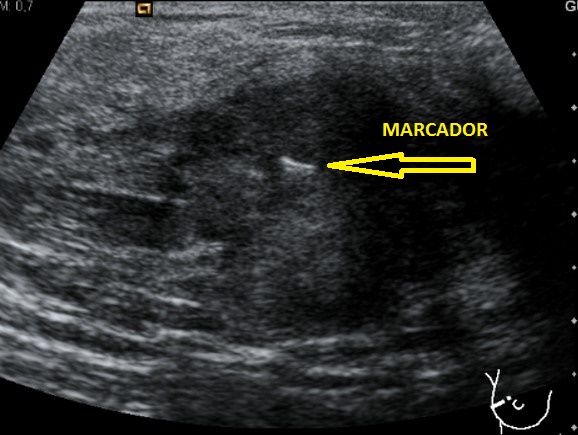

En la imagen 1 ya puedes observar la semiología típica de este tipo de tumores, homogeneidad, hipoecogenicidad y forma pseudotriangular. Aquí ya nos debe llamar la atención, está muy pegado a la carótida, la anatomía adyacente está conservada, en la imagen 2 te lo marco con flechas rojas para que lo ubiques bien.

Te pido ahora que observes aténtamente la imagen 7 y la imagen 8 y en las lesiones marcadas con flechas amarillas. En la imagen 7 puedes ver imágenes nodulares en ambos lóbulos tiroideos, son nódulos de los que habitualmente encontramos en un bocio multinodular, compara ahora con la imagen de la imagen 8, así a bote pronto, ¿Te llama algo la atención?…mira bien las imágenes…tómate un momento, no sigas leyendo…

Sí, efectivamente, la lesión de la imagen 8, que es a la que le hemos estado dedicando este tiempo, parece estar localizada fuera del tiroides, en su LTD, concretamente en su porción más profunda, como pegada a él…aunque el aspecto pueda ser similar a un nódulo normal, en este caso, la localización de la lesión, también nos va a ayudar en el diagnóstico.